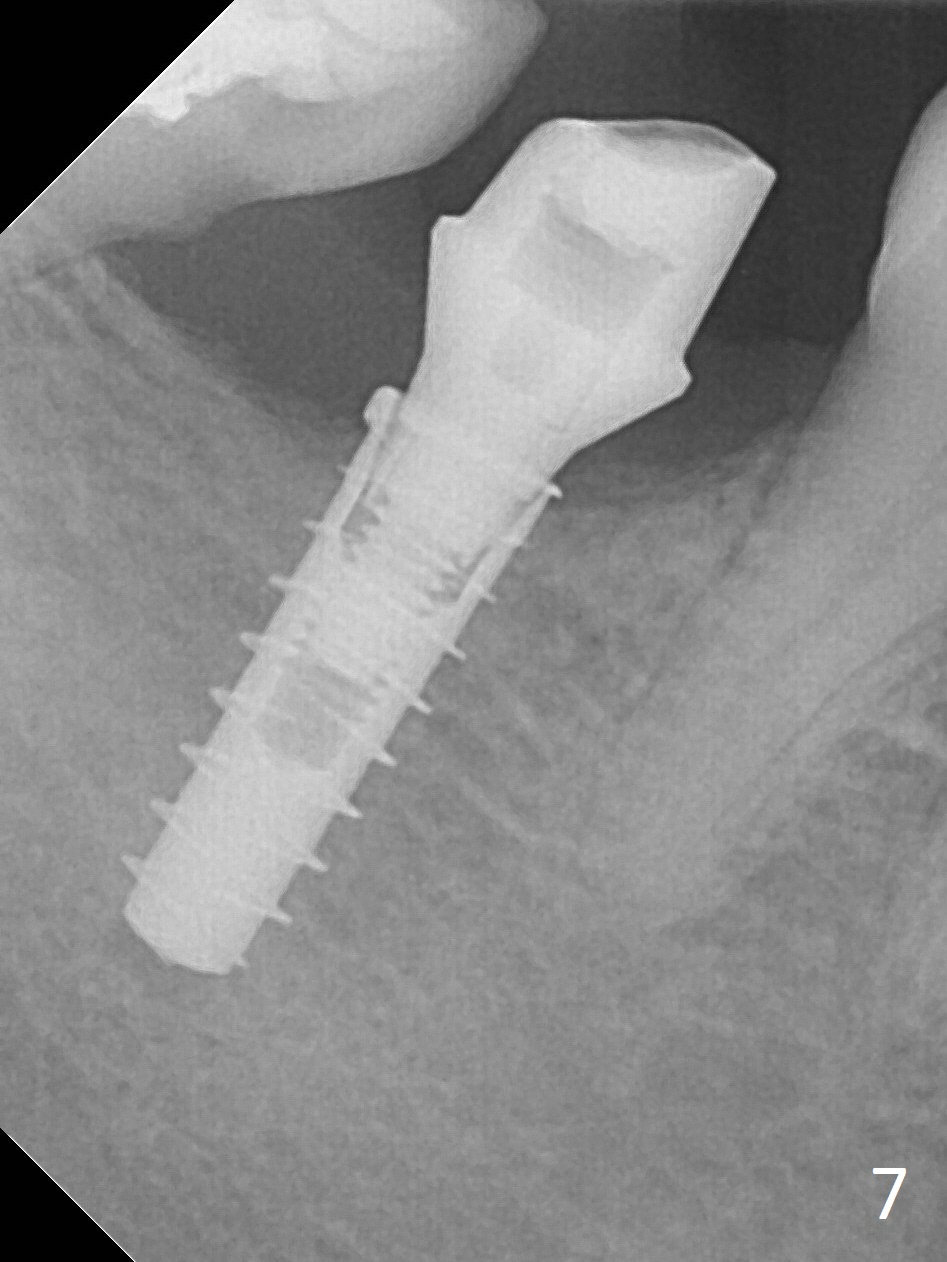

There is no apparent bone loss 4 months postop (Fig.7), related to the advantage of the narrow implant (less traumatic).  The crown/abutment is loose 2.5 years post cementation due to incomplete abutment seating (Fig.8 < (no clearance between the abutment (A) and the mesial crest (C))).  A 6x3 mm healing abutment is placed.  When the patient returns, try in the smallest abutment with 2 mm cuff in the Planning Kit and place probably a 4x4(3) mm pair abutment from 5x4(2) mm existing one.  Torque and take PA with sensor 1 to confirm seating before impression. Or use 5.5 mm profile drill before reseating the crown/abutment.